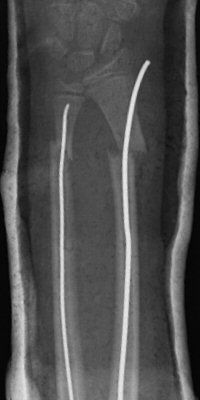

Monteggiafraktur, opererad med TEN-spik